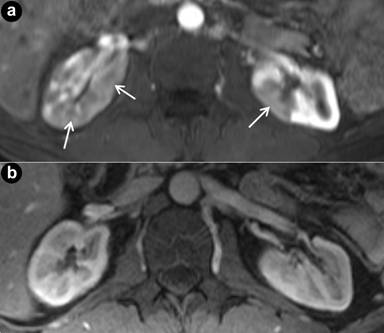

An MRI of the abdomen obtained 5 months after completion of induction corticosteroids revealed homogeneous enhancement in the pancreas. There was mild dilatation of the extrahepatic bile duct but this had improved compared to his pre-treatment MRI. The appearance of the abnormal renal cortical enhancement was also improved compared to the pre-treatment MRI (Figure 3). Diffusion weighted MRI revealed a significant increase in the ADC values in left (from 1.065 x10-3 mm/sec2 to 2.024 x10-3 mm/sec2; i.e., 90.0% increase) and right (from 1.027 x10-3 mm/sec2 to 1.854 x10-3 mm/sec2; i.e., 80.5% increase) kidneys after corticosteroid therapy (Figures 4 and 5). For reference the ADC values of the adjacent normal renal parenchyma were (right kidney: 2.105 x10-3 mm/sec2, left kidney: 2.021 x10-3 mm/sec2, comparable to the values before treatment).

Figure 4. Axial apparent diffusion coefficient (ADC) maps from diffusion weighted MR images at the level of the kidneys. Pre- treatment ADC values in left kidney was 1.065 x10-3 mm/sec2 and post-treatment ADC values increased to 2.024 x10-3 mm/sec2 (90.0% increase) which is compatible with favorable response to steroid treatment. |

Figure 5. Axial apparent diffusion coefficient (ADC) maps from diffusion weighted MR images at the level of the kidneys. Pre-treatment ADC values in right kidney was 1.027 x10-3 mm/sec2 and post-treatment ADC values increased to 1.854 x10-3 mm/sec2 (80.5% increase) which is compatible with favorable response to steroid treatment. |